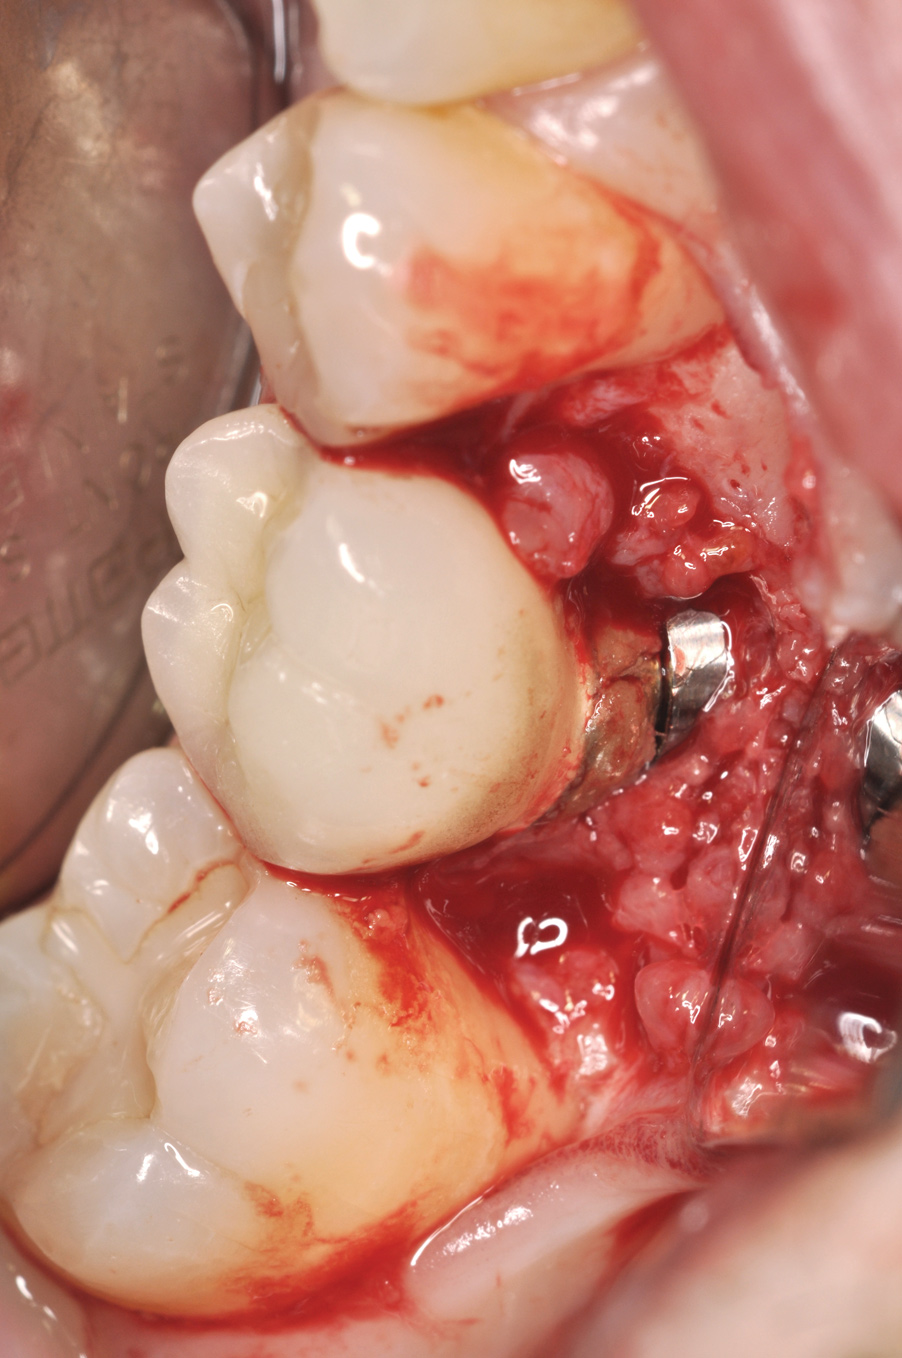

Fig 14. Clear resin cement left on the implant abutment.

Fig 15. Implant abutment following cement removal.

If all implant-supported crowns could be designed for screw retention, no discussion of excess cement would be necessary. However, screw retention is not always possible depending on the location of the access opening and because of the unesthetic appearance in anterior restorations or the mesial/distal angulation of the implant compromising the path of insertion (Figure 12). Residual cement left after crown cementation on implants can lead to peri-implant inflammation, peri-implantitis, and eventual loss of the implant (Figure 13 through Figure 15).25 The presence of lingering excess cement can encourage the development of bacterial colonization and peri-implantitis. Conversely, when too little cement is used, voids in the cement layer can occur and the prosthesis can become loose.26 The deeper the implant crown margin, the more difficult it is to remove excess cement.27

Radiopaque cements that contain zinc phosphate and zinc oxide (with and without eugenol) should be considered to help identify excess interproximal cement; however, this should be used secondarily to proper margin height and careful removal of cement during cementation. Resin cements lack the same opacity as zinc-containing cements and have been shown to be the most difficult to remove.28 Often in the process of removing this excess cement, the abutment surface becomes scratched and damaged, potentiating further plaque accumulation.29

Several modifications in abutment design and cementation have been suggested. Placing vent holes in the abutment during fabrication or leaving most of the screw-access chamber open for access has reduced the amount of cement that expresses out into the sulcus.26 It is also beneficial to extraorally express excess cement on an abutment replica prior to final crown seating to minimize complications. If retrievability is desired with cementable implant crowns, weaker cements (eg, zinc oxide eugenol) should be used first and progressively changed until the desired retention is achieved.